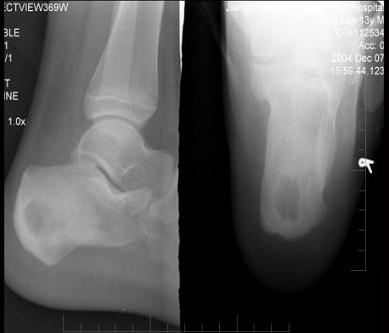

问题 13岁男性患者,右跟骨疼痛不适3周,无发热等其他不适,右跟骨侧、轴位摄片如图示,最可能的诊断是 ( )

选项 A、右跟骨血管瘤 B、以上都不是 C、右跟骨骨囊肿 D、右跟骨骨巨细胞瘤 E、右跟骨结核

答案 E